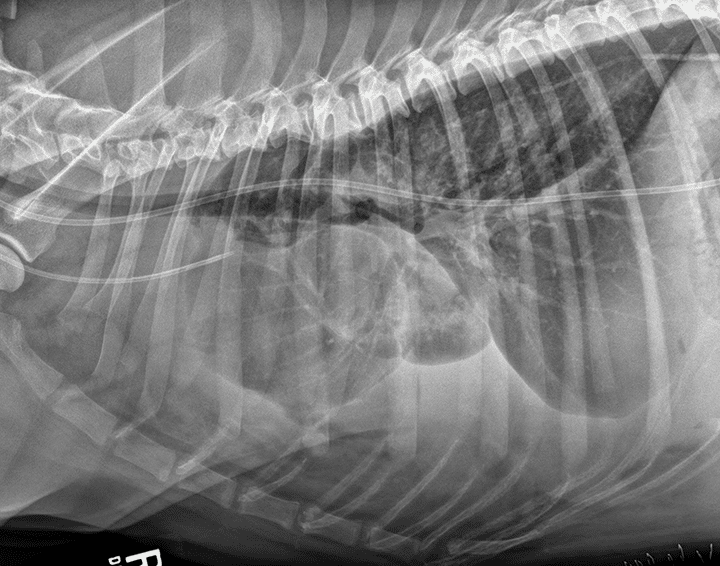

图1-图3是基于表3影像学征象的胸腔积液剖析。

图2患有乳糜胸的犬右侧位胸片,伴有中度胸腔积液。存在与图5中相似的特征。此外,心脏轮廓边疆消逝,尾背侧肺叶呈圆形。图中金属钉来自胸导管闭塞手术。